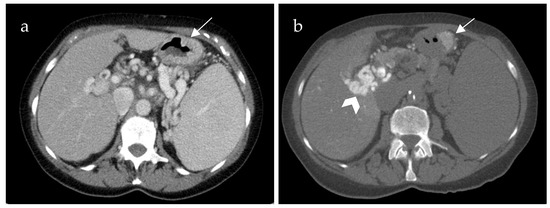

Inflow into esophageal, gastric and small bowel varices differed significantly between patients with PVCT (p = 0.021, p = 0.016 and p = 0.031, respectively) compared to patients without PVCT. In patients with PVCT, esophageal varices were fed solely by the SV in 75% (n = 9, example shown in Figure 3), solely by the mesenteric vein system in 8% (n = 1) and by both systems in 17% (n = 2, example of this rare case shown in Figure 4). Patients without PVCT showed a more equal distribution of inflow hemodynamics: esophageal varices were fed by solely the SV system in 22% (n = 2), by solely the SMV system in 22% (n = 2) and by both systems in 56% (n = 5, example of this is shown in Figure 5). In patients without PVCT, gastric varices were fed by the SV (22%, n = 2), by the SMV (11%, n = 1) or both (22%, n = 2). In contrast, 59% of the patients with PVCT (n = 7) showed gastric varices which were fed only by the SV. In 33% of cases (n = 4), both the SV and SMV drained into gastric varices. No inflow into gastric varices solely from the SMV was detected. These results were statistically significant (p = 0.016).

Figure 3. Computed tomography mesenterico-portography (a) and computed tomography splenoportography (b) of a 58-year-old patient with portal hypertension, portal vein thrombosis and portal vein confluence thrombosis. Esophageal varices (EV) are detected after contrast injection into the splenic artery ((b), white arrow). The EV do not show contrast enhancement after contrast injection into the superior mesenteric artery.